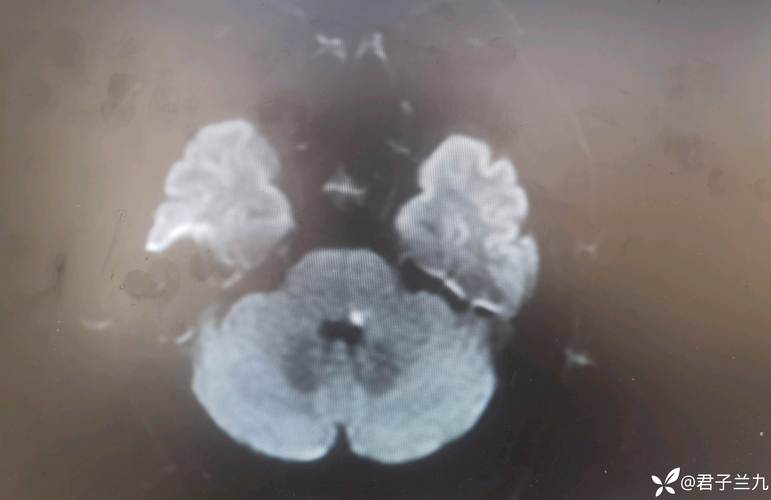

脑梗,全称“脑梗死”,俗称“中风”的一种,是由于脑部血管阻塞,导致局部脑组织缺血、缺氧而发生坏死。

- 病因:最常见的原因是血栓或栓子(脱落的斑块、血凝块等)堵塞了脑血管。

- 后果:堵塞区域的脑细胞会迅速死亡,导致相应的神经功能缺损,如偏瘫、失语、意识障碍等,严重时可致命。